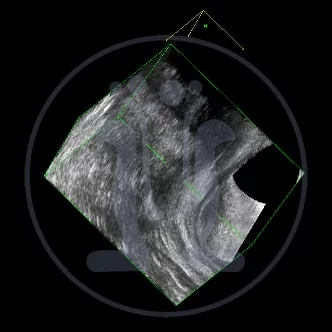

Ασθενής 44 ετών που εξετάσαμε δεύτερη φορά μετά από 14 μήνες έμεινε αθεράπευτος γιατί κανείς δεν ήθελε να τον αναλάβει. Είχε δύο ράμματα seton σε λάθος θέση ενώ στην σωστή θέση δεν υπήρχε ράμμα seton. Πολλαπλές επεμβάσεις είναι απαραίτητες για την τελική θεραπεία του προβλήματος του.